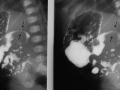

Hemorragia adrenal em recém nascido

Set de 2024.

2.742